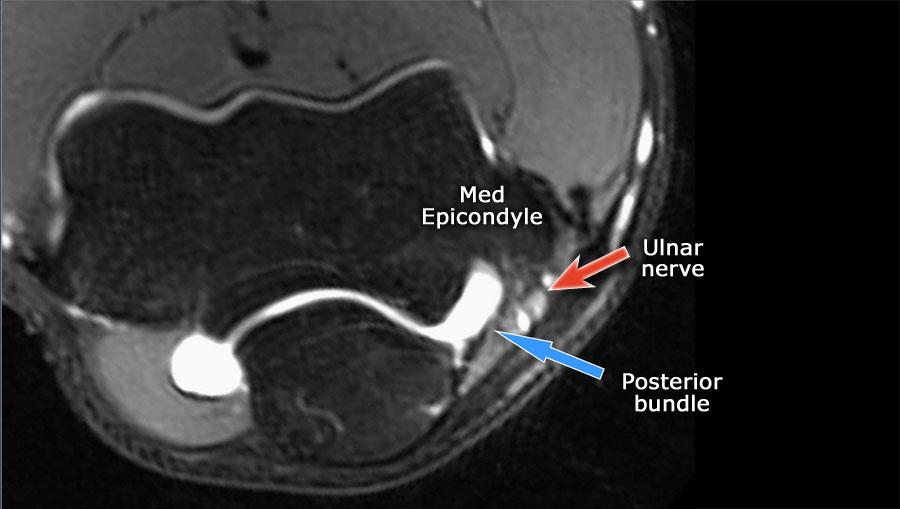

Luôn sử dụng hình ảnh mặt cắt ngang (axial) khi nghiên cứu các dây chằng, đặc biệt là dây chằng bên trụ (UCL).

- Nếu bạn nhìn vào mỏm trên lồi cầu trong, bạn sẽ nhận thấy bó sau như một cấu trúc mỏng (mũi tên xanh).

- Notice the ulnar nerve sitting in the cubital tunnel.

- The posterior bundle forms the floor of the cubital tunnel.

- A retinaculum covers the cubital tunnel.

- Lưu ý rằng bó trước dày hơn nhiều (mũi tên trắng).

- Bạn có thể thấy sự khác biệt giữa dây chằng trước và dây chằng sau mặc dù chúng tạo thành một dây chằng duy nhất.

- Khi đi về phía xa, chúng ta sẽ thấy chúng hợp nhất lại để bám vào củ sublime.